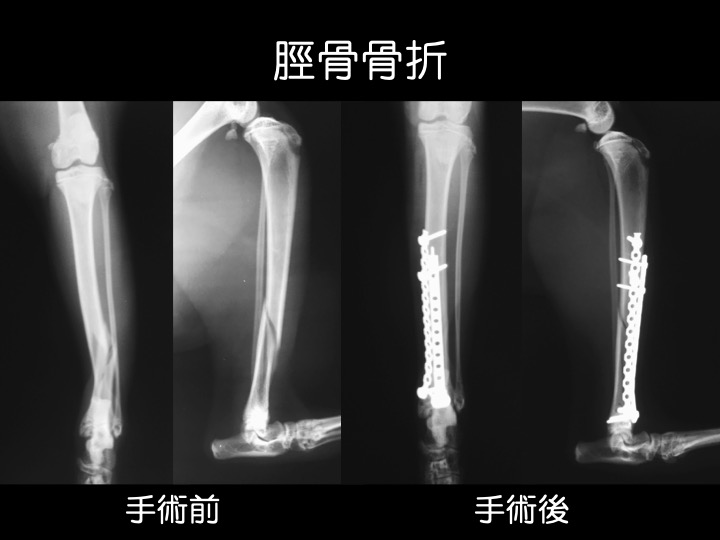

・猫ちゃんは、階段や高所からの落下事故による骨折が多い傾向にあります。

・脛骨すなわち「スネ(脛)」の周囲は筋肉などが薄く血流に乏しいため、この箇所の骨折は癒合不全が起こりやすいと言われています。

・写真のような、体の外に装具がついた固定具を「創外固定」と呼びます。骨の癒合にあわせて段階的に外していき、最終的には全て外して完治となります。